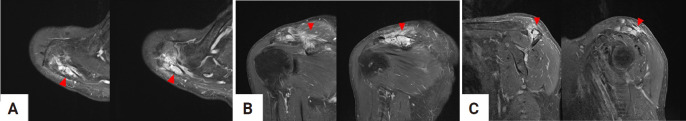

Epithelioid hemangioma of bone is a rare benign vascular tumor. Because of the locally destructive clinical presentation and the presence of atypical histologic features with increased mitotic activity and necrosis, it is often misdiagnosed as low-grade malignant epithelioid hemangioendothelioma or high-grade malignant epithelioid angiosarcoma. Correct diagnosis through imaging studies and histopathological examination is mandatory to determine the appropriate course of treatment, as the prognosis differs from that of other malignant hemangioma tumors. A 69-year-old male who presented with intractable shoulder pain caused by epithelioid hemangioma in the acromion of the scapula was treated with tumor curettage. This paper reports a good result with a review of the relevant literature.